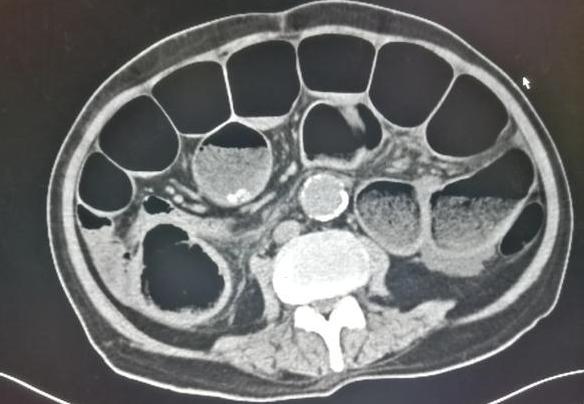

来医院全面检查后发现了右侧结肠癌:

还好,没有发现明显转移,及时做了根治手术。